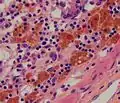

Micrograph showing melanosis coli, which appears as brown pigmentation in the macrophages in the lamina propria.

Micrograph showing melanosis coli, which appears as brown pigmentation in the macrophages in the lamina propria. Micrograph of melanosis coli. H&E stain.

Micrograph of melanosis coli. H&E stain. Micrograph of melanosis coli. H&E stain.

Micrograph of melanosis coli. H&E stain.